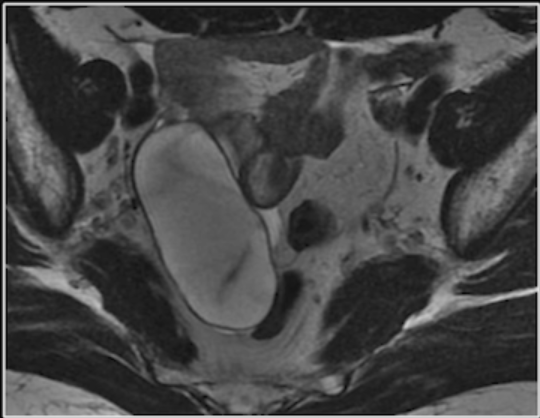

Cisto de inclusão peritoneal.

Estrutura cística volumosa que se amolda na pelve

Engloba o ovário.

Finas septações.